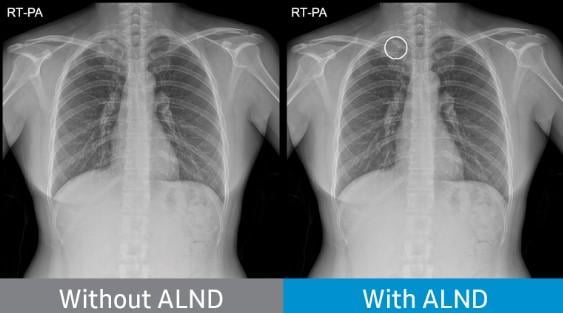

Chest radiograph without Auto Lung Nodule Detection (ALND) and chest radiograph with lung nodule marked.

October 28, 2021 — NeuroLogica Corp. announced it has received Food and Drug Administration (FDA) 510(k) clearance for its Auto Lung Nodule Detection (ALND) tool. The offering provides an on-device, computer-assisted detection (CADe) solution for detecting pulmonary nodules from 10 to 30mm in size through an artificial intelligence (AI) algorithm.

It is designed to aid the physician in reviewing PA chest radiographs of adults and is part of S-Station, an operation software installed on Samsung Digital X-ray Imaging systems.

- Aiding the reader's diagnosis by indicating the location of suspected lung nodules on chest X-ray images (posteroanterior chest radiographs). The deep-learning technology has been clinically verified in multiple university hospitals and has been approved with a sensitivity of 80% or more. Investigators at these hospitals – Freiburg University Hospital, Freiburg, Germany; Massachusetts General Hospital, Boston, Massachusetts; Samsung Medical Center, Seoul, South Korea; and Severance Hospital, Seoul, South Korea – retrospectively identified 600 chest radiographs with lung cancer and 200 normal chest radiographs.

Clinical evaluation results have demonstrated that all readers' nodule detection performances using ALND have increased with statistical significance.